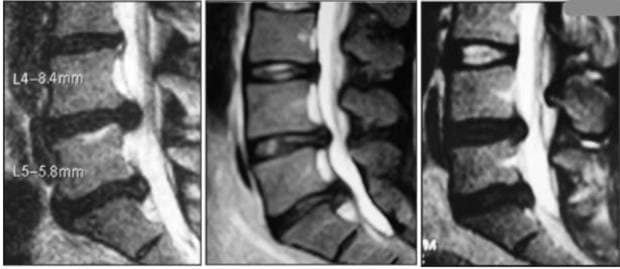

Хірургічна тактика при багаторівневих зміщеннях поясничних міжхребтових дисків

Мета. Покращити результати хірургічного лікування поясничних больових синдромів та радикулопатій, викликаних багаторівневим зміщенням міжхребтових дисків у попереково-крижовому відділі хребта. Матеріали та методи. Протягом 2014–2018 років ми обстежили та лікували 3045 пацієнтів з болем у попереку та радикулопатією, викликаною зміщенням міжхребтових дисків у поперековій області. Сімдесят два відсотки пацієнтів з багаторівневим зміщенням міжхребтових дисків були обстежені та проліковані в Дніпропетровській обласній клінічній лікарні ім. І.І. Мечникова, 21% пацієнтів – у медичному центрі «Ендоскопічна нейрохірургія» та 7% пацієнтів були прооперовані в медичному центрі «Клініка сімейної медицини». Середній вік пацієнтів склав 42,6 ± 5,4 року. Всі пацієнти пройшли неврологічне обстеження з функціональними пробами, комп'ютерною та магнітно-резонансною томографією, спондилографією, електронейроміографією. Ефективність обраного методу хірургічного лікування оцінювали за шкалою VAS, статичне та динамічне тестування функції хребта до втручання та через 2–3 тижні, через 2–3 місяці та через 3–5 років після операції. Дні непрацездатності були взяті до уваги. Результати. Пацієнти перенесли пункційну лазерну мікродискектомію (PLM) та ендоскопічну мікродискектомію (EDE) (p <0,05) з найбільш значним полегшенням больового синдрому, а мікродискектомія з інструментами була пов'язана зі зменшенням больового синдрому на всіх стадіях. Показники статичної та динамічної функції хребта з використанням тесту Шобера, латерофлексії, розгинання в динаміці також були значно кращими у пацієнтів після ПЛМ та ЕДЕ порівняно з іншими методами хірургії. Найменша кількість днів непрацездатності спостерігалася у пацієнтів, які перенесли PLM (30,7 ± 6,3 дня) та EDE (24,6 ± 5,2 дня). Максимальна кількість днів непрацездатності була у 34 пацієнтів після мікродискектомії з інструментарієм – 64,5 ± 10,7 дня. Висновки. При виборі хірургічної тактики для двох гриж, розташованих на несуміжних рівнях, клінічні прояви та розміри другої грижі повинні бути вирішальними. При порівнянні ефективності хірургічного лікування багаторівневих гриж міжхребтових дисків у попереково-крижовому відділі хребта найкращі результати були отримані з використанням методів EDE та PLM.